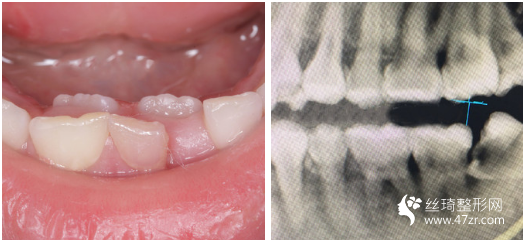

3.武漢愛齒爾口腔門診部張郭龍主治醫(yī)師案例展示

一直以來,我算是一個(gè)對(duì)自己要求比較高的人,見不得自己有任何的瑕疵,就連牙齒也不行。 所以在我開啟牙齒矯正路途前的三個(gè)月里,我托了較為多人進(jìn)行行業(yè)摸底(哈哈哈其實(shí)就是找個(gè)靠譜的醫(yī)生幫我做

很感謝我遇到了不錯(cuò)的醫(yī)生,在這方面臨床經(jīng)驗(yàn)比較豐富,醫(yī)生說我的矯治過程進(jìn)展的較為順利,矯正速度真的是較為快呢,牙齒不齊整體也在調(diào)整牙齒咬合狀態(tài)了?,F(xiàn)在笑的時(shí)候更加自信了,所以牙弄齊了以后我打算在做個(gè)美白,平時(shí)抽煙牙齒也很黃